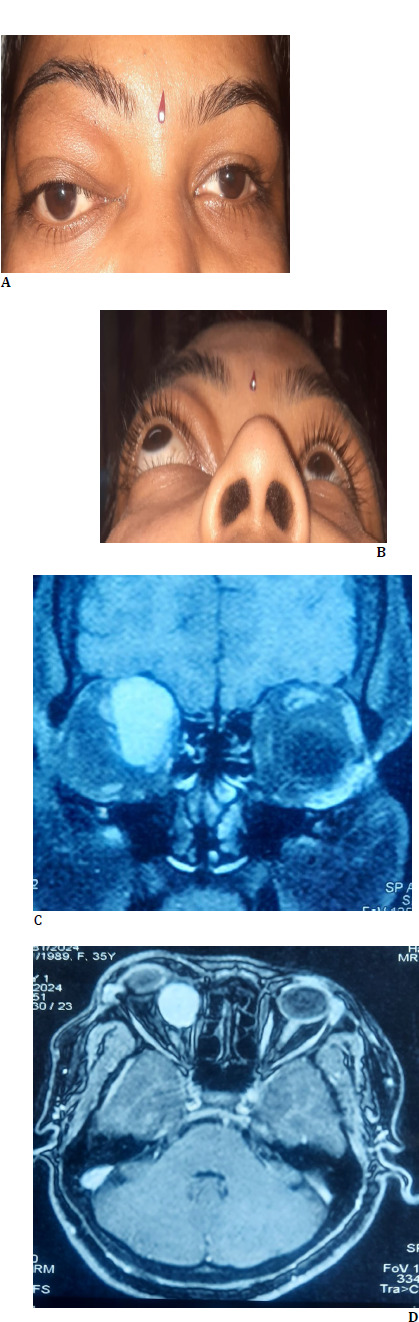

We report a problematic case of solitary fibrous tumor of the orbit in an anemic patient who presented with painless, progressive outward protrusion of the right eye. Magnetic resonance imaging (MRI) orbit and brain with contrast showed a well-defined intraconal lesion in the superomedial aspect of the right orbit. The lesion was excised using a vertical eyelid split orbitotomy with minimal blood loss. Histopathological and immunohistochemical examination showed the features of a solitary fibrous tumor. This case highlighted that with careful surgical planning, total removal of a large vascular tumor could be done with less bleeding, especially in an anemic patient in whom an iota of hemorrhage was life-threatening.